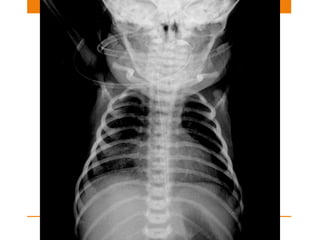

Endotracheal tube

• USE: Assisted ventilation

• The tip of an ETT will be in a satisfactory position if it

approximates to the level of the medial ends of the

clavicles

• Ideal position is 5–7 cm above an adult’s carina when the

head is held in the neutral position.

• And if carina is not visible in 95% people it is situated

at T5-T7 vertebra

Tracheostomy tube

• Tracheostomy tube lies parallel to the long axis of the

trachea

• The tip lies several centimeters well above carina

• The inflated cuff should not extend lateral walls of